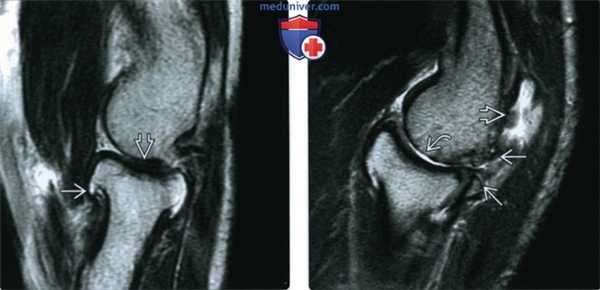

(Слева) МРТ, сагиттальная проекция, режим Т2: признаки ОА локтевого сустава от легких до умеренных, включая остеофиты и легкое истончение хряща.

(Справа) МРТ, сагиттальная проекция, режим Т2: ОА сочленения между головкой лучевой кости и головкой мыщелка плечевой кости со свободными телами в растянутом заднем завороте. Признаки остеофитоза визуализируются сзади. Также имеются признаки субхондрального склероза и утраты хряща. Визуализация мелких свободных тел при МРТ или рентгенографии затруднена.